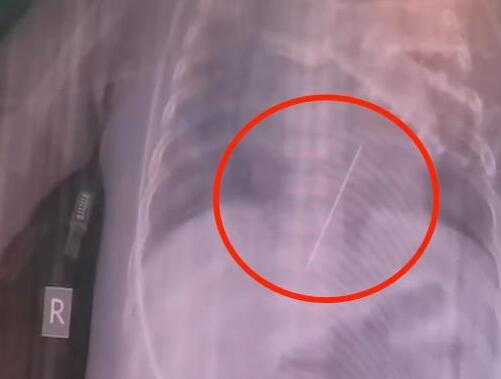

导读:女婴心脏扎进一根4厘米绣花针 真相离谱实在是太荒唐了。8月1日,陕西西安,一名5个月大的女婴因抽搐和意识障碍被送往西安某医院。

面对这一情况,医生们推测了两种可能的情景。第一种可能是孩子在玩耍的过程中,这枚钢针通过体外不小心扎入体内。第二种可能是孩子不小心将绣花针误吞,然后绣花针穿过胃壁,最终刺入左心室。女婴心脏扎进一根绣花针!